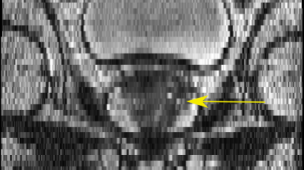

Fig. 4: SR result for anisotropic SRGAN using real data, yellow arrow indicates suspicious cancer region

Figure 4 is an example of axial and coronal views. The HR views portray the difference in resolution between the in-plane axial slice and the coronal and sagittal through-plane slices. The SR views show the anisotropic SRGAN outputs on the real HR data. The arrows in the top row of Figure 4 point to a suspicious region within the axial prostate. The LR axial image obtained by taking a through-plane slice from a coronal volume has lost all information about this region. The SR image is able to reconstruct the high frequency content and provides valuable edge and texture information. The anisotropic SRGAN method is able to improve the through-plane resolution by 8x while incurring only a slight resolution loss in the in-plane slice.